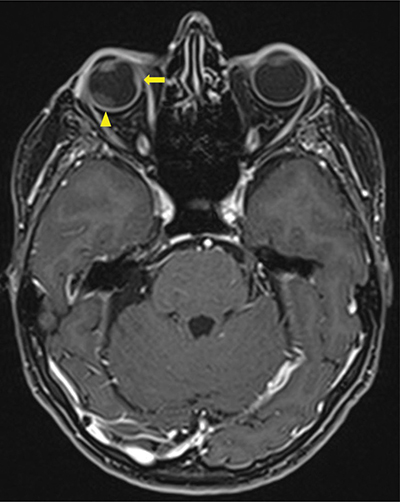

Figure 2

Contrast enhanced Axial T1 Dixon MRI-scan showing a second intra-orbital metastasis (arrow) invading all layers of the eyeball including sclera and a secondary retinal detachment (arrowhead).

A magnetic resonance image (MRI) demonstrated a 16.5 × 10.7 mm right intraorbital mass of superolateral topography invading all of the ocular globe layers (Figure 1), and a second medial 8 × 3.7 mm right intraorbital mass (arrow, Figure 2 T1, Figure 3 T2). The posterior sclera and the periorbital fat were invaded, with partial right retinal detachment (arrowhead, Figure 2 T1, Figure 3 T2).